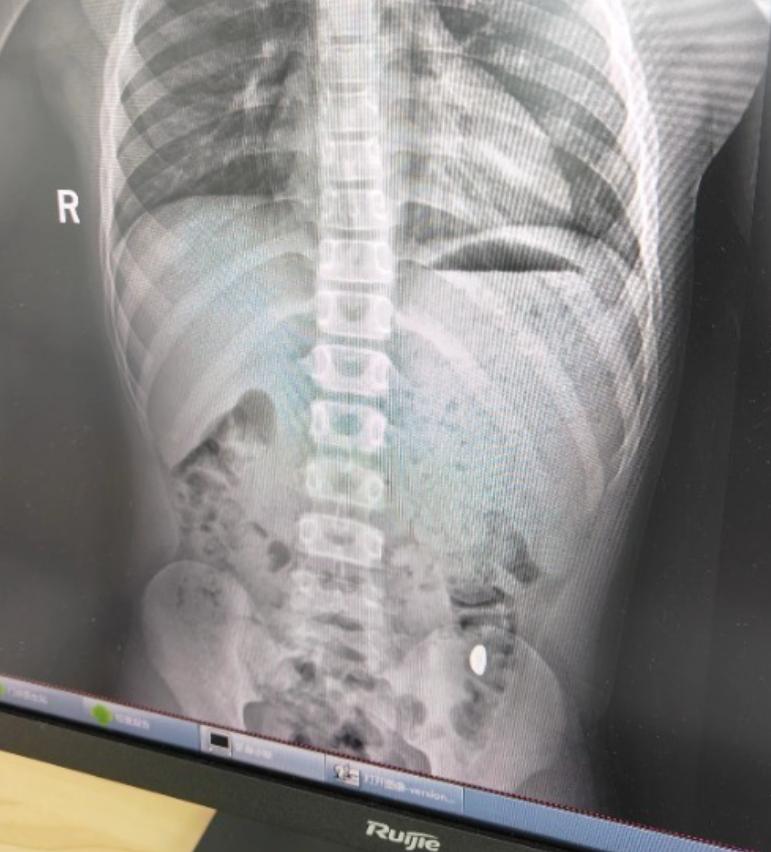

昆山市第五人民醫(yī)院門診病歷單顯示,患兒5天前誤吞約10克黃金,其間解兩次大便未發(fā)現(xiàn),目前無腹痛、嘔吐等癥狀,診斷結(jié)果顯示胃內(nèi)有異物。

右下加亮點(diǎn)為金豆。